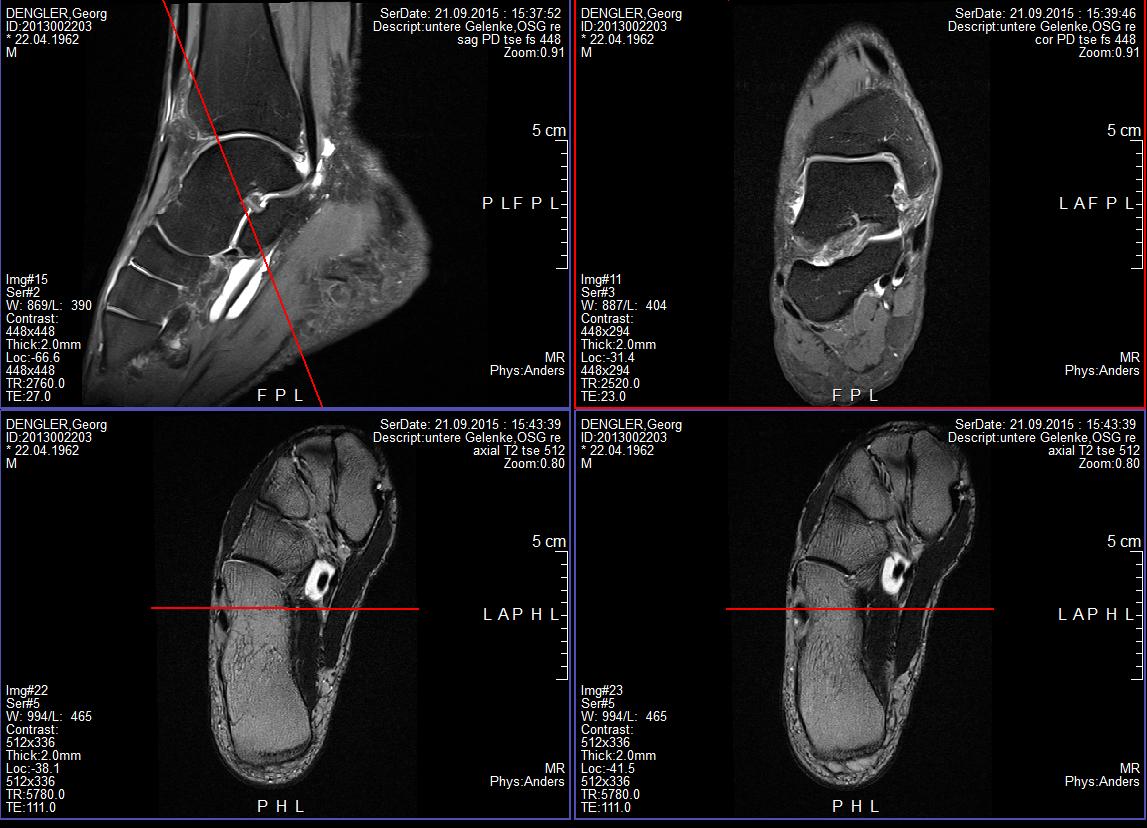

6. MRT Bild rechtes Sprunggelenk: Befunde hier: [ATTACH]41643[/ATTACH]

7. MRT Bild linkes Sprunggelenk: Follow up MRT, erstes MRT wurde am 18.9.2015 gemacht, gleicher Befund